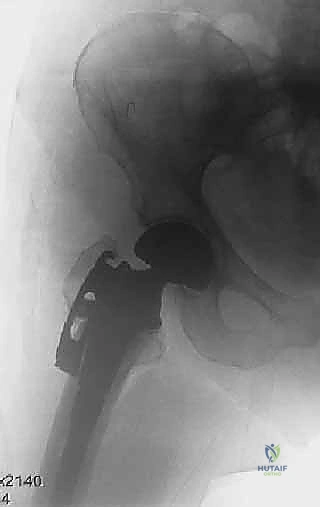

* إذا كان التدمير كبيراً، يستخدم الدكتور هطيف دعامات معدنية خاصة (Reconstruction Rings/Cages) يتم تثبيتها بمسامير في عظام الحوض السليمة لإنشاء سقف جديد للمفصل.

* يتم تثبيت الكوب البلاستيكي أو المعدني (Socket) باستخدام الأسمنت العظمي لضمان ثباته الفوري.

الخطوة 5: رد المفصل والاختبار

يتم إدخال الرأس الجديد في التجويف الجديد (Reduction). يقوم الدكتور هطيف باختبار المدى الحركي للمفصل في جميع الاتجاهات للتأكد من استقراره التام وعدم قابليته للخلع، والتأكد من تساوي طول الساقين.